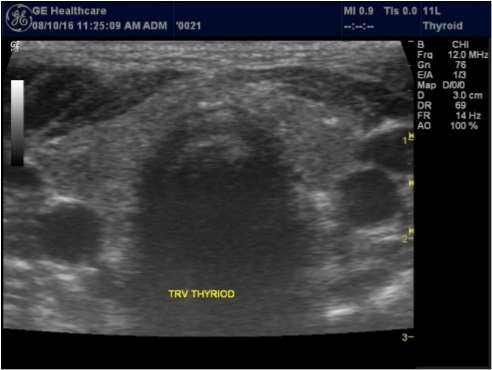

The superficial location of the thyroid gland renders it ideal for ultrasound examination 8. High resolution grey scale images can easily be obtained using high frequency transducer. In the transverse view, normal thyroid gland has the butter fly appearance, with left and right lobes connected with a narrow isthmus, Figure 1A. Both lobes can be imaged separately in the longitudinal plan, Figure 1B

Figure 1A.Normal thyroid gland transverse view